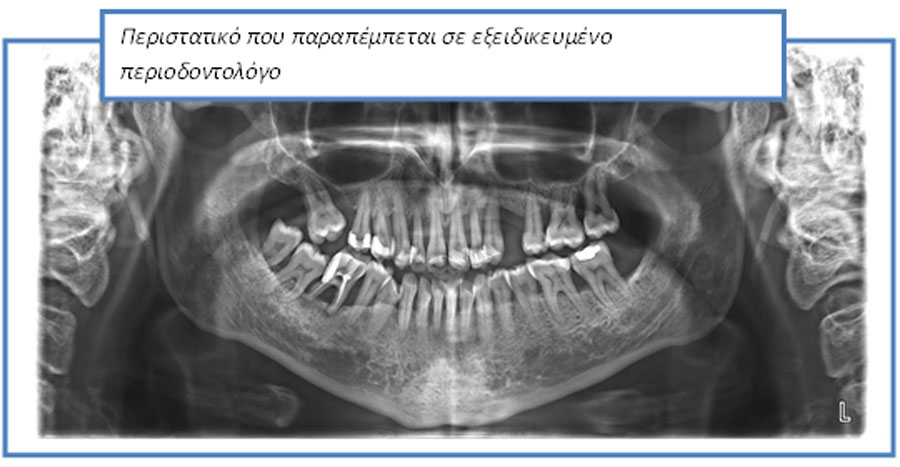

Στις μέρες μας, ένα μικρό ποσοστό του πληθυσμού εμφανίζει βαριά περιοδοντική καταστροφή και επομένως χρειάζεται απόλυτα εξειδικευμένες υπηρεσίες.

Οι περισσότεροι από εμάς χρειάζονται περιοδοντολογική φροντίδα, δηλαδή πρόληψη και θεραπεία νόσων – λοιμώξεων που προέρχονται από μικροοργανισμούς που στην πλειονότητα των περιπτώσεων βρίσκονται στο στόμα μας.

Περιστατικά που αντιμετωπίζονται στο ιατρείο μας